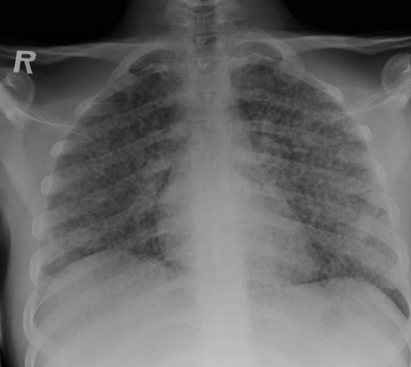

What should you do before treating patients for latent TB?

Make sure patients do not have active disease -> get a CXR

What are some of the clinical manifestations of miliary/disseminated TB? CXR?